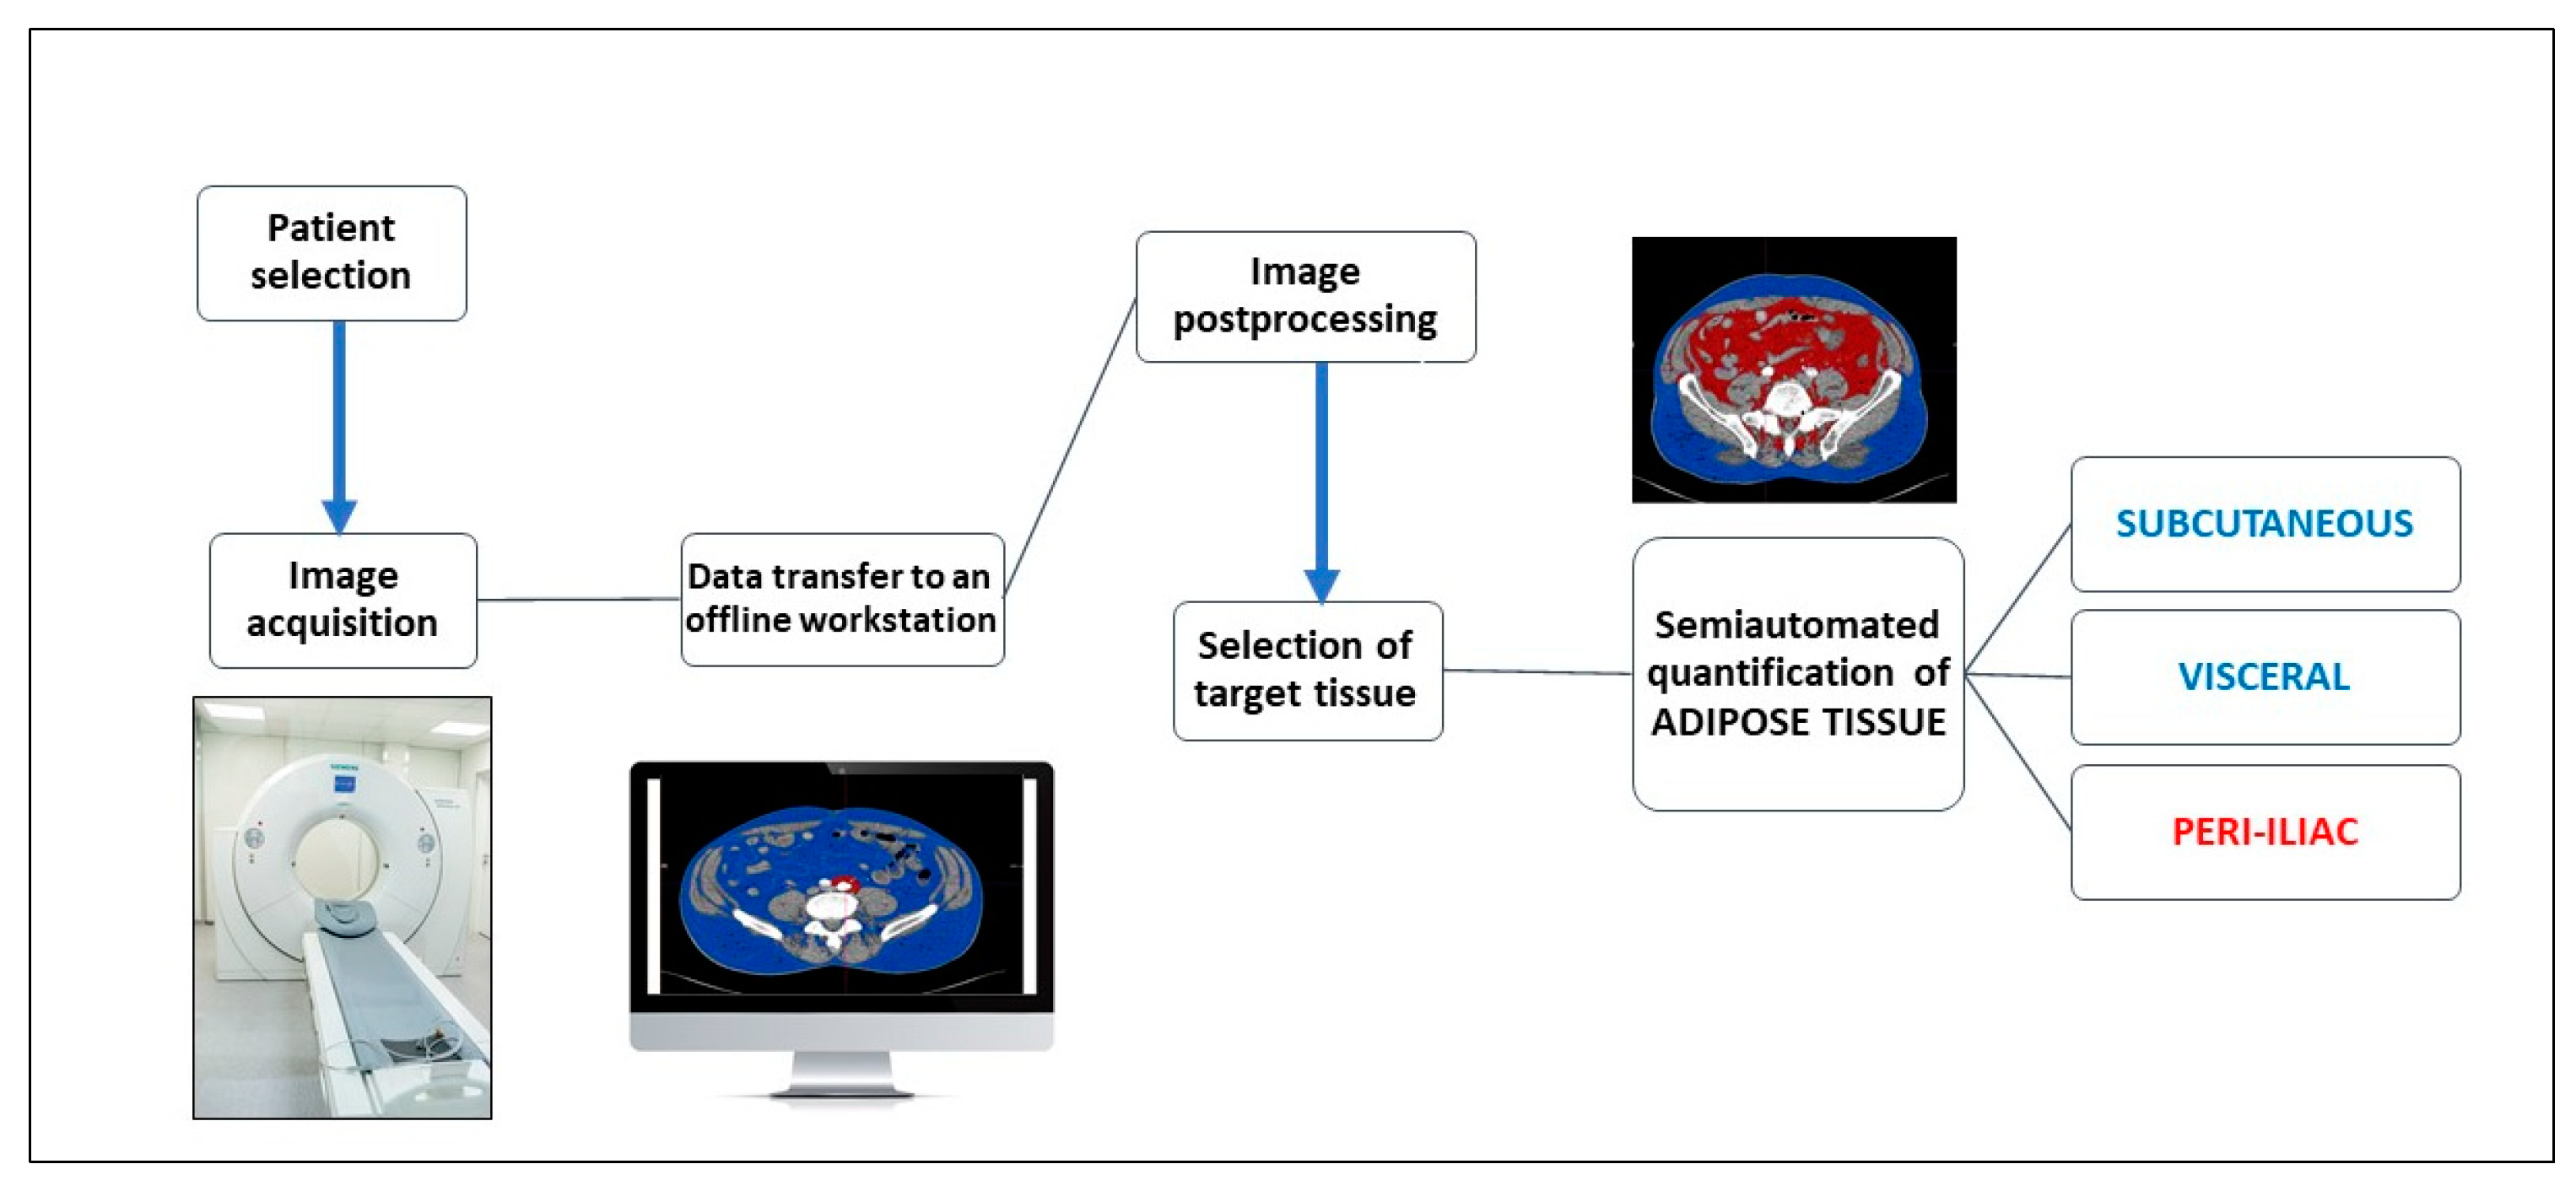

2. Materials and Methods

2.2. Computer-Aided CT Image Postprocessing

2.3. Assessment of the Periiliac Adipose Tissue

2.4. Assessment of The Subcutaneous and Visceral Adipose Tissue